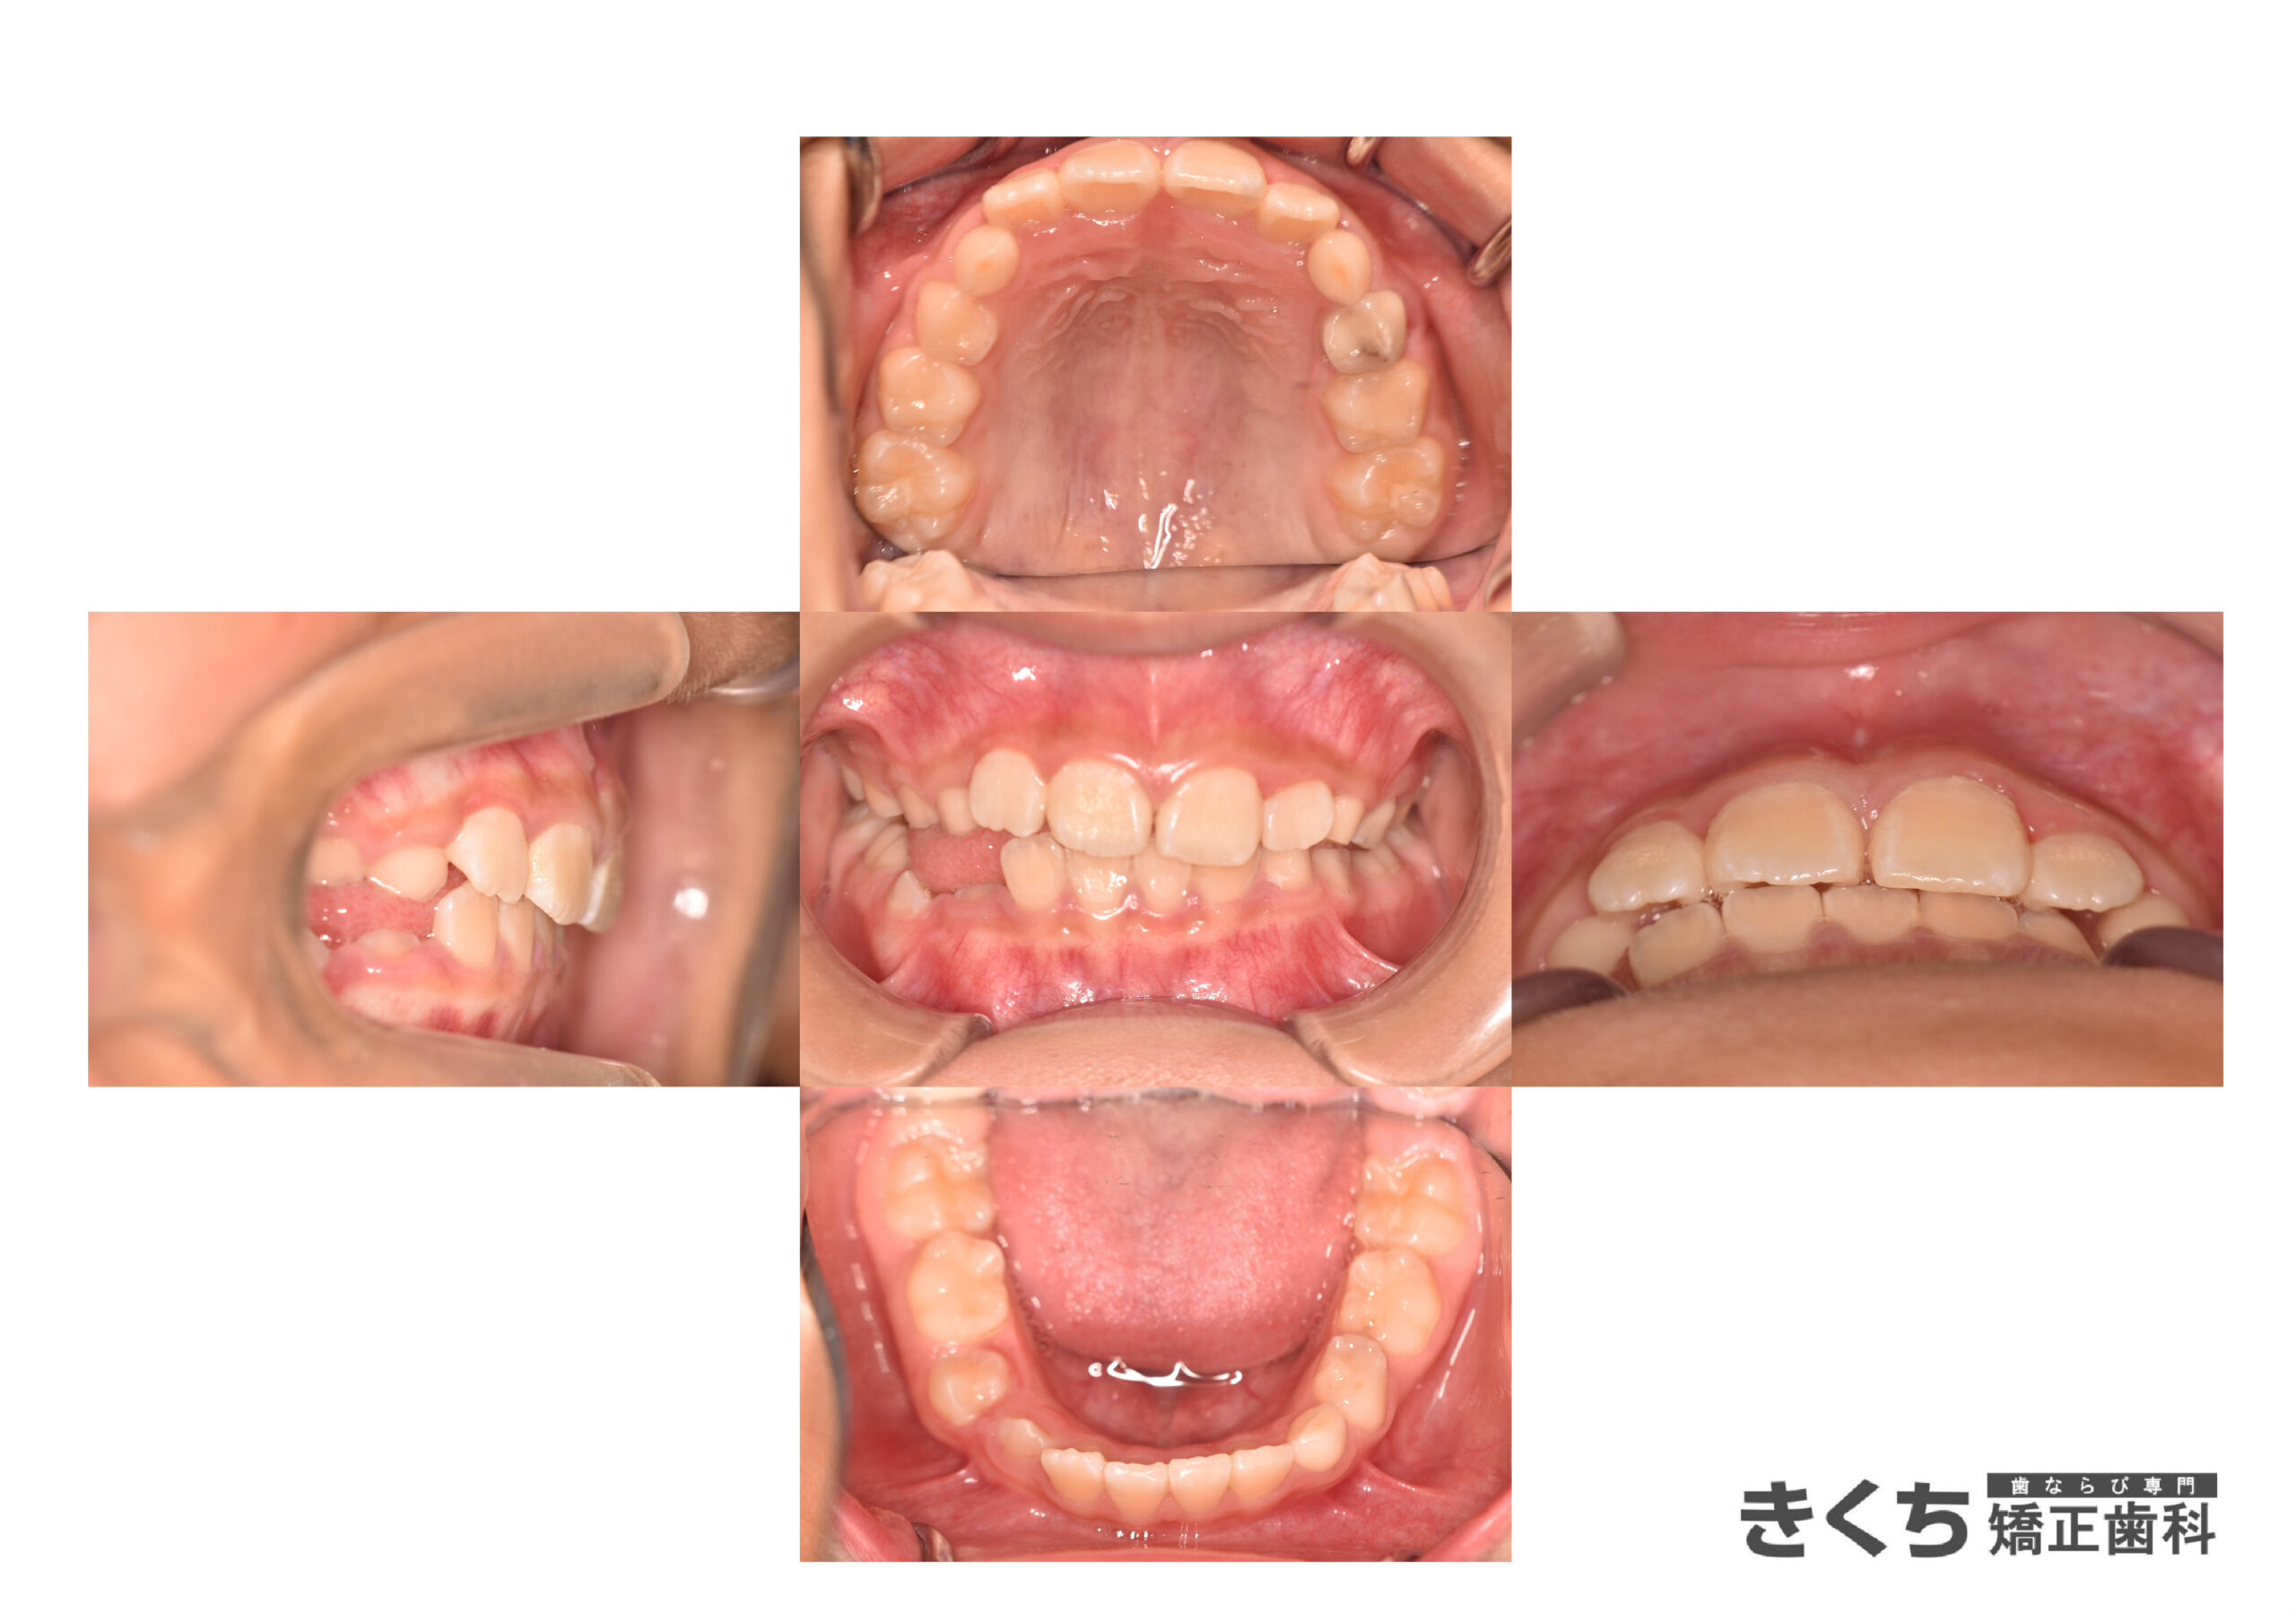

↓↓↓↓↓↓↓ 6ヶ月後

口腔筋機能 の改善だけで、気にしていたかみ合わせが自然に改善しました。